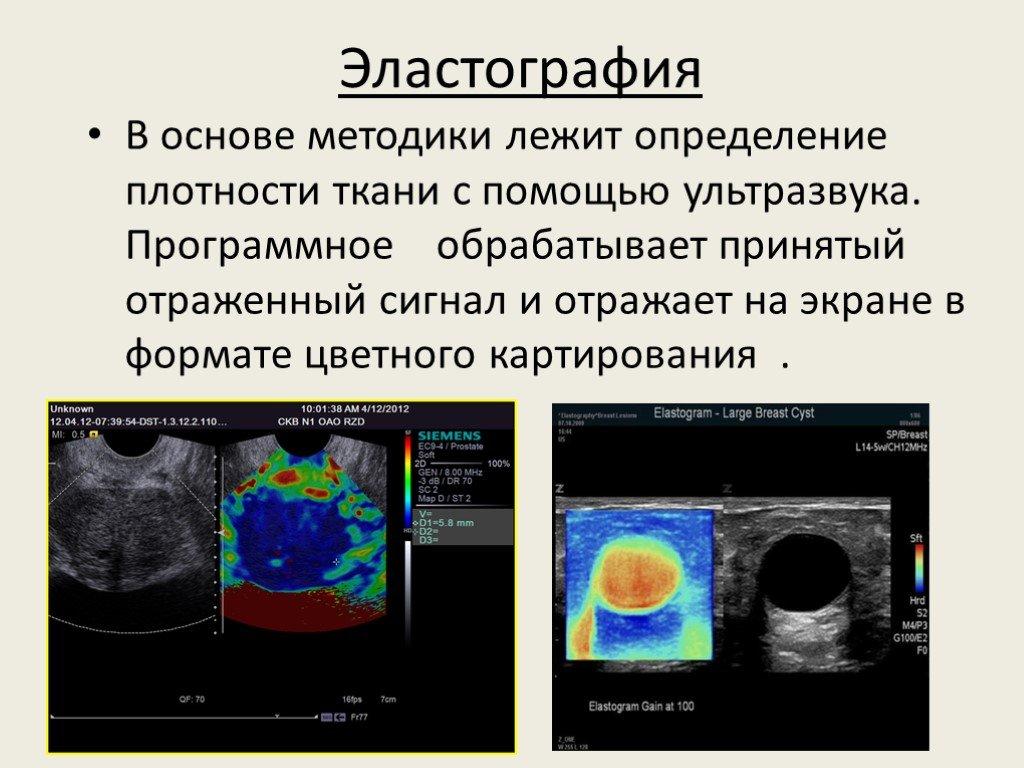

Эластометрия брюшной полости – это современный метод диагностики, который позволяет оценить состояние тканей органов в брюшной полости с помощью ультразвуковых волн. Это исследование помогает выявить различные заболевания на ранних стадиях, таких как цирроз печени, фиброз, воспалительные процессы и другие патологии, что способствует своевременному назначению эффективного лечения.

УЗИ органов брюшной полости и эластография печени на Mindray Resona i9